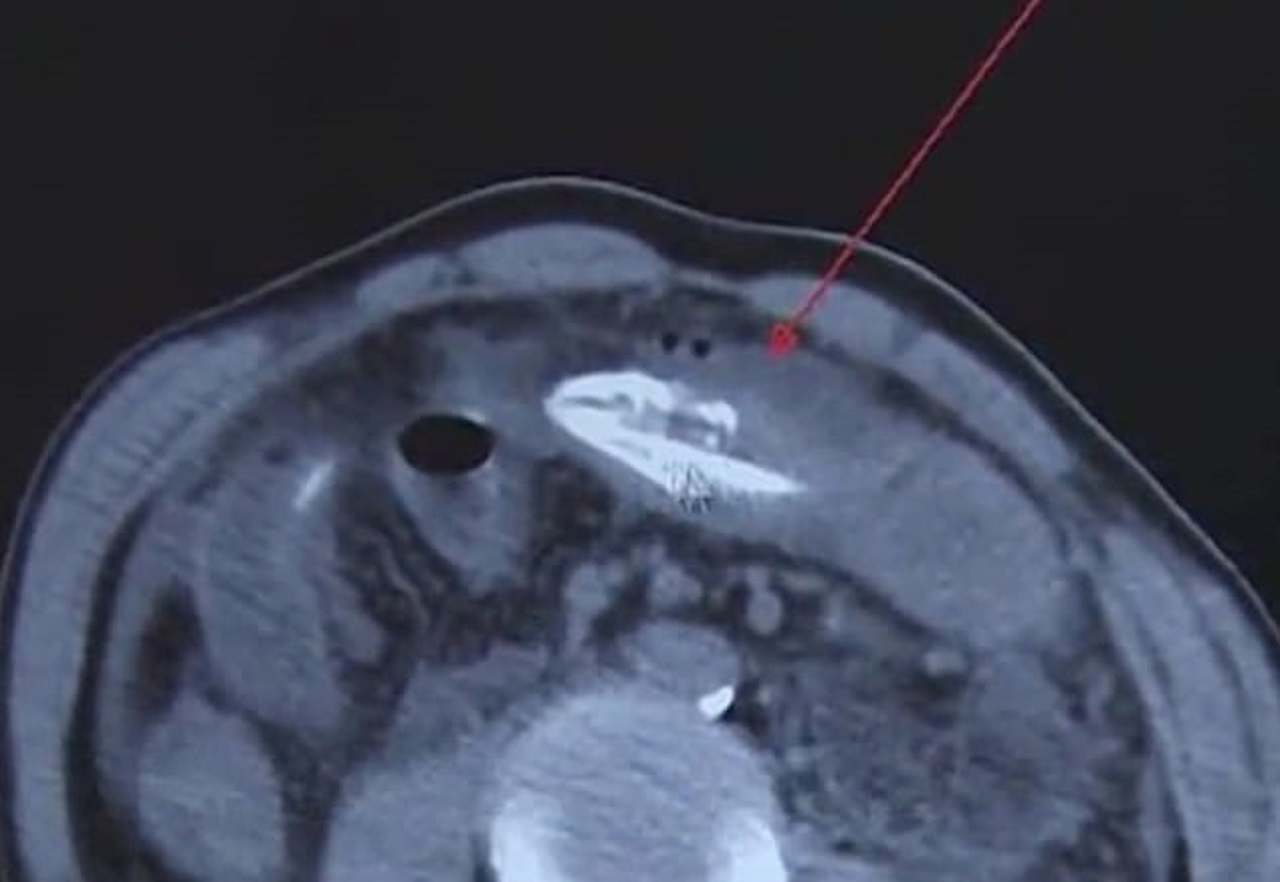

رویداد۲۴ یک مرد میانسال چینی که از شکم درد شدید خود کلافه شده بود پس از مراجعه به بیمارستان با صحنهای عجیب روبه رو شد. پزشکان پس از انجام آزمایش CT یک مارماهی مرده ۱۶ اینچی را که در معده این مرد گیر کرده بود پیدا کردند.

این مرد پس از شکم درد شدید خود به بیمارستان «هوانگ جیانگ» در دونگ گوان واقع در استان گوانگ دونگ چین مراجعه کرده بود. پزشکان جراح پس از یک عمل جراحی موفق به خارج کردن این جانور از معده این بیمار ۵۰ ساله شدند. دکتر لی، یکی از پزشکان تیم جراحی گفت: «ما مشکوک به وجود یک جسم خارجی در معده این بیمار بودیم. پس از انجام آزمایش سی تی اسکن یک جانور را در معده این بیمار مشاهده کردیم. حین فرآیند لاپروسکوپی متوجه شدیم این جانور یک مار ماهی است. ظاهرا این مرد طبق یک روش درمان سنتی برای پاکسازی اقدام به قورت دادن این مارماهی کرده بود.»

بنا به گفته پزشکان بخشهایی از معده این بیمار شدیدا عفونت کرده بود. پس از پایان عمل جراحی و بهوش آمدن این مرد اعتراف کرد که اقدام به قورت دادن این مارماهی کرده است.

گفتنی است؛ در حالی پزشکان موفق به خارج کردن این جانور از معده این بیمار چینی شدند که بنا به گفته پزشکان در صورتی که این عمل جراحی کمی دیرتر انجام میشد درصد احتمال مرگ این بیمار بسیار بالا بود.